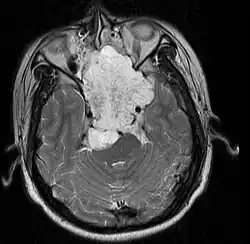

| MRI of extensive clival chordoma in 17-year-old male patient, axial view. Tumor in the nasopharynx extending from nasal cavity to brainstem posteriorly is clearly visible. | |

Chordoma is a rare slow-growing neoplasm (cancer) that arises from cellular remnants of the notochord in the bones of the skull base and spine. The evidence for the notochordal origin of chordoma is the location of the tumors (along the neuraxis), the similar immunohistochemical staining patterns, expression of brachyury, and the demonstration that notochordal cells are preferentially left behind in the clivus and sacrococcygeal regions when the remainder of the notochord regresses during fetal life.

In layman's terms, chordoma is a type of bone cancer, and is classified as a sarcoma.[1] Chordomas are sometimes mistakenly referred to as a brain, brainstem or spinal cord tumors due to their location near those critical structures, but they are not derived from nervous tissue.

Chordomas can arise from bone in the skull base and anywhere along the spine. The two most common locations are cranially at the clivus and in the sacrum at the bottom of the spine.[2] Very rarely, chordomas present outside of the skull base or spine; these are called extra axial chordomas.[3]